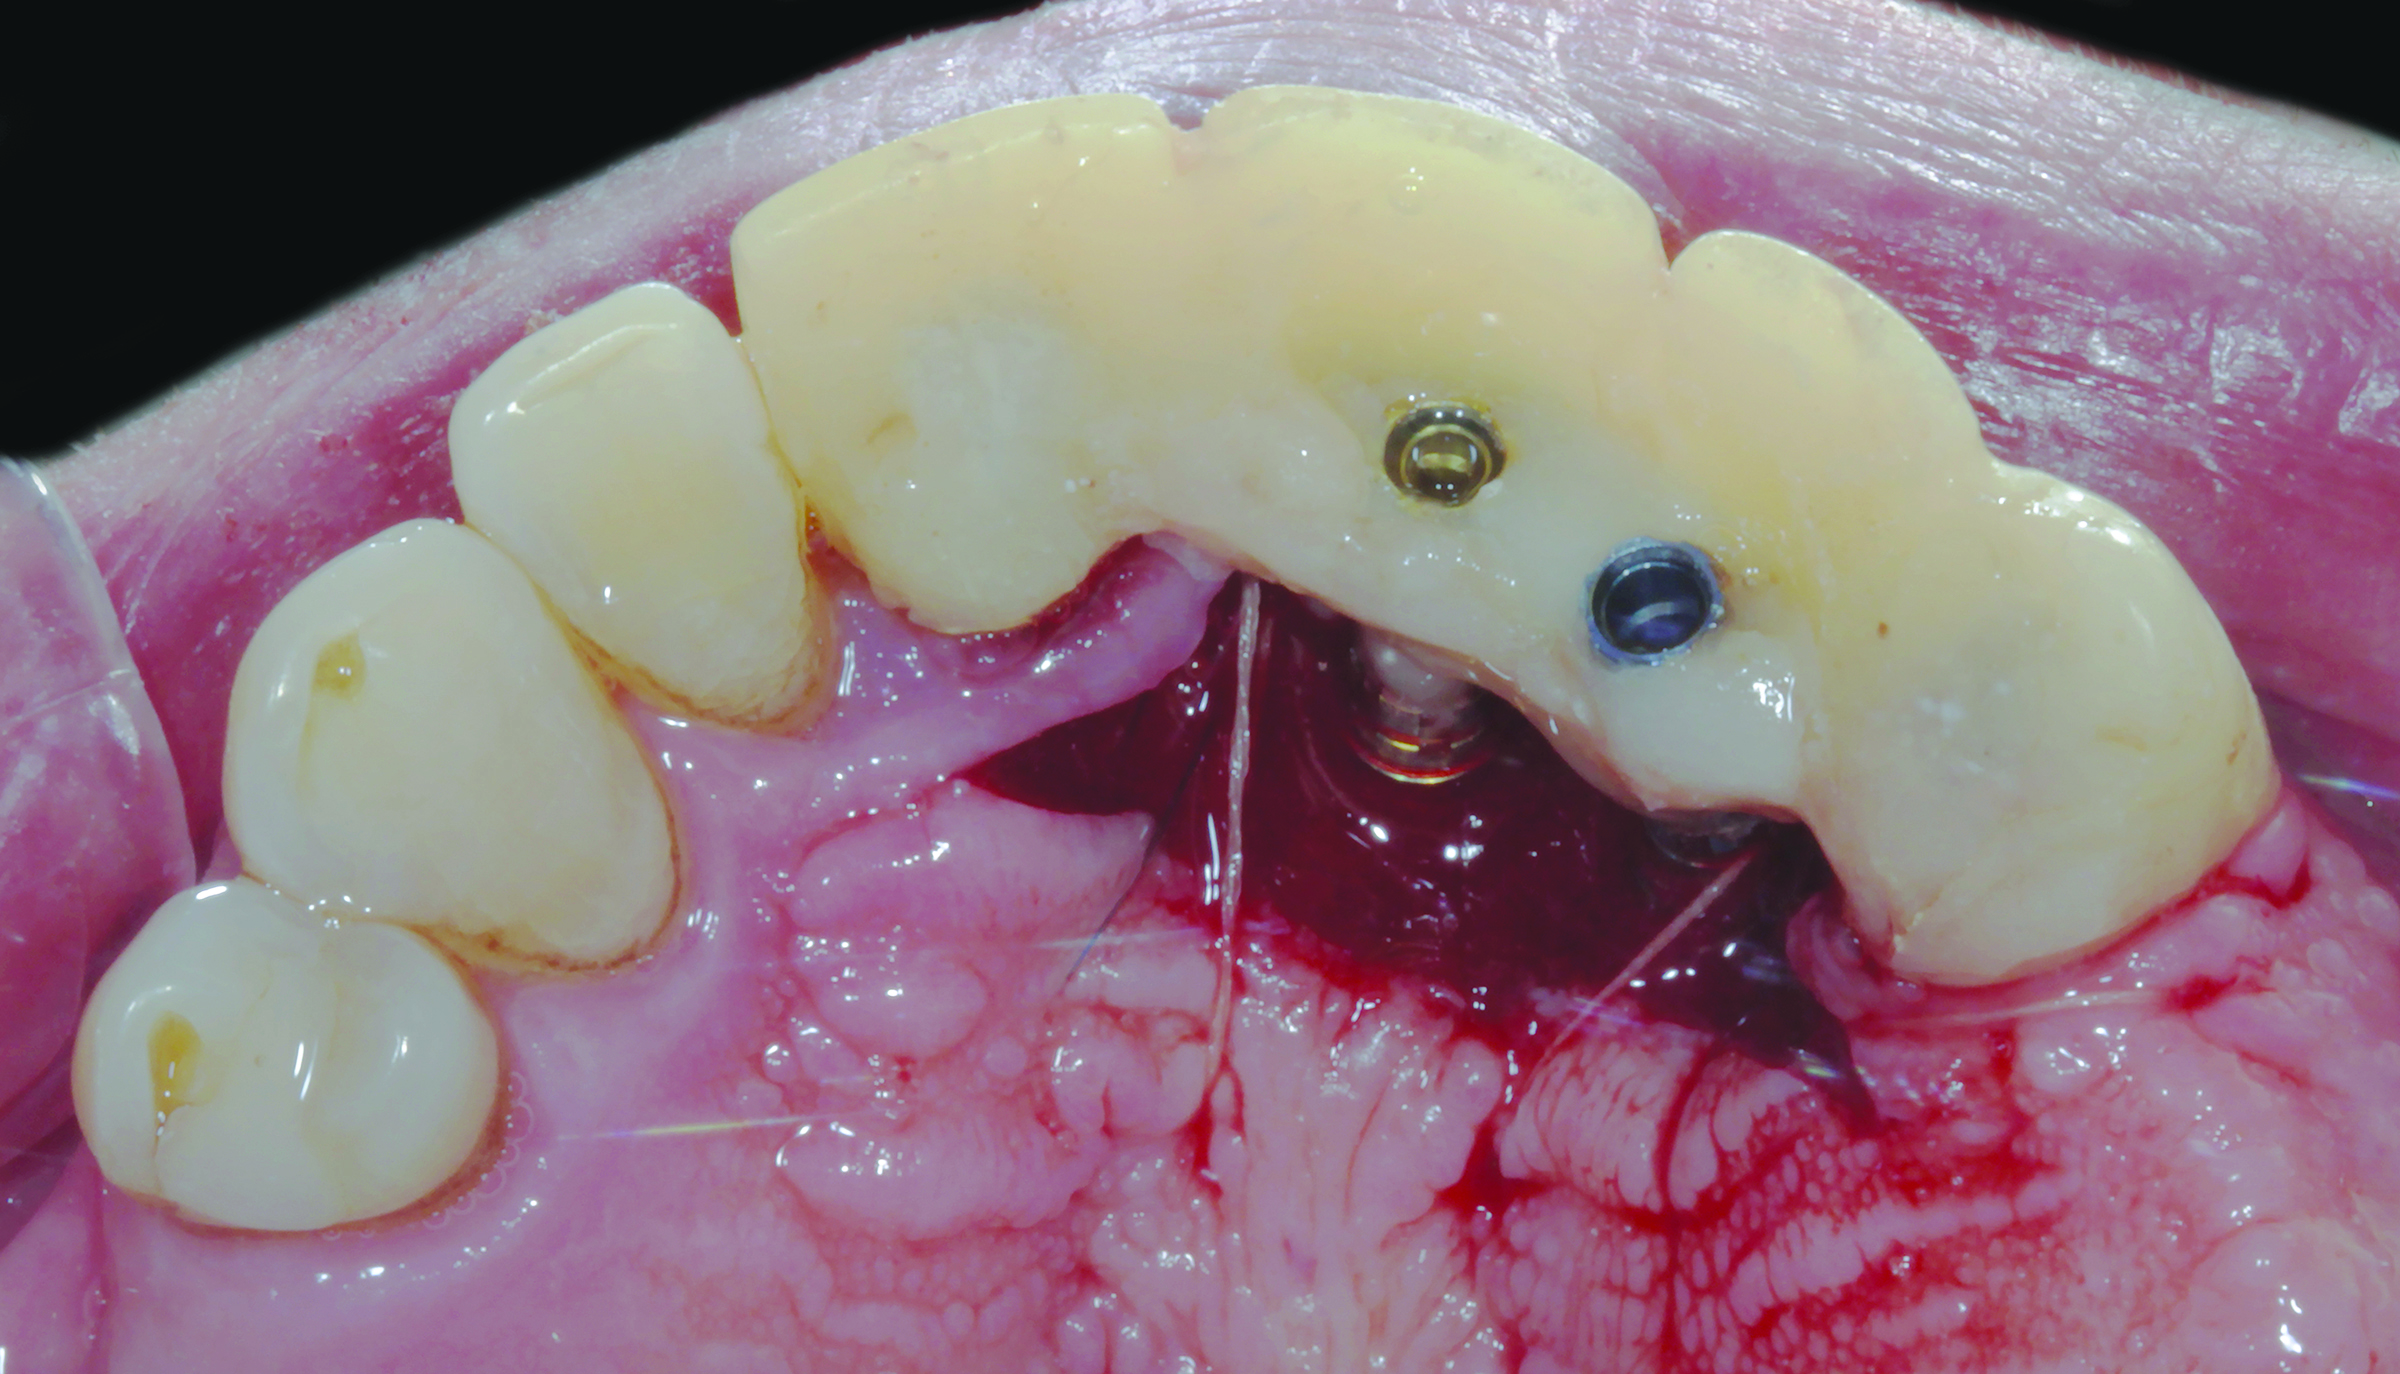

Fig 3. The try-in of the laboratory-processed PMMA shell has the abutments in place prior to connecting and pickup. A portion of a palate acts as a stop for acrylic resin support.

Figure 3

Fig 4. Before final impression making, the ovate pontic receptor sites and emergence profiles can be seen. They are created with the aid of the provisional prosthesis.

4

Figure 4